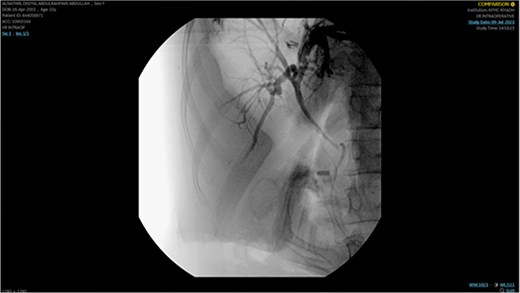

A single segmental biliary stricture was identified in the common hepatic duct. Biliary sphincterotomy was conducted as a form of post-ERCP prophylaxis, and a plastic stent was placed in the right hepatic duct and ventral pancreatic duct, as shown in Fig. 5. Visualization of the biliary tree confirmed the patency of the ducts.

Demonstrating placement of a plastic stent in the right hepatic duct and ventral pancreatic duct as post-ERCP prophylaxis.